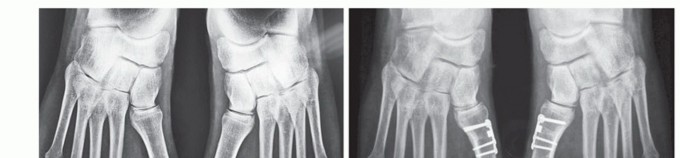

In our experience, the procedure reliably and reproducibly corrects the 1-2 IMA, HVA, and increased DMAA (FIG 5) and can be useful as a complementary procedure in severe cases (FIG 6).

FIG 5 • A. Preoperative and postoperative radiographic images of a right foot with hallux valgus with increased DMAA, treated by the biplanar chevron osteotomy. The correction of the DMAA and the sesamoid position is easy to see. The valgus of the great toe was also satisfactorily corrected. B. In these images, we can see the correction obtained with the biplanar distal chevron osteotomy. The cephalic fragment was 6 mm laterally dislocated to correct the IMA and the sesamoid position. The DMAA and HVA were corrected to normal values. In the lateral view, we can see the size and position of the screw used in the fragment fixation. C. Lateral views of a patient treated by the biplanar distal chevron osteotomy, where we can see both the plantar and dorsal arms of the osteotomy, the position of the screw used in its fixation, and the alignment of the cephalic fragment with the metatarsal diaphysis resulting from the dorsal fragment resection.

FIG 6 • Preoperative (A) and postoperative (B) radiographic images of a patient with severe hallux valgus

deformity with increased DMAA treated by the combination of a proximal opening wedge osteotomy, a distal

biplanar chevron osteotomy, and a proximal phalangeal closing wedge “Akin” osteotomy.